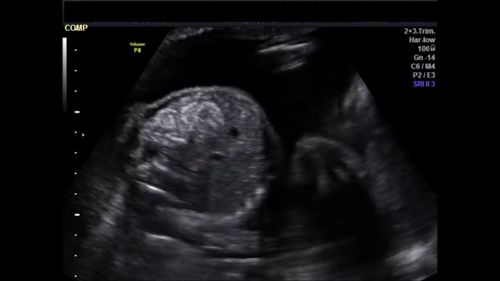

This image quiz focuses on the kidneys. Can you identify the abnormality seen in these ultrasound images of the fetal abdomen?

Challenge your diagnostic skills: What's going on with the kidneys in this fetus?